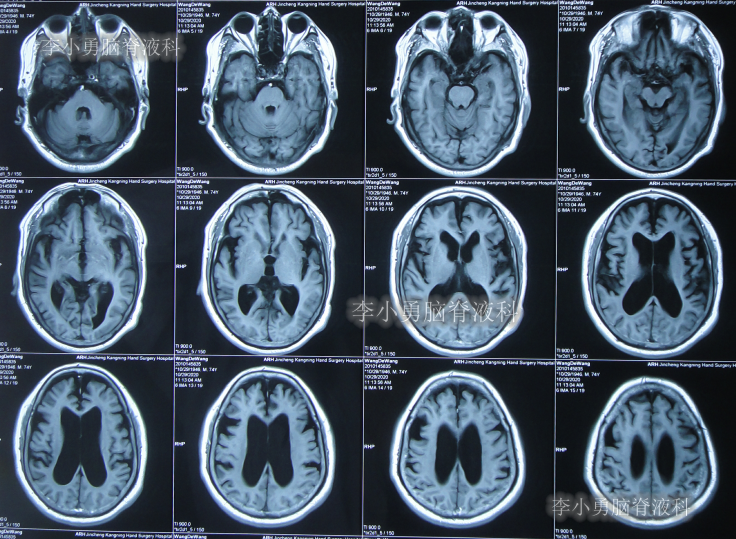

2020年10月29日(发病已8年),因症状一直没有得到改善且呈进行性加重趋势,查头部核磁示脑积水(图-1)。

图-1:2020年10月29日头部核磁